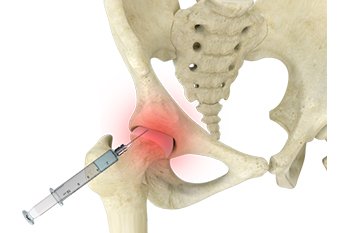

إذا لم تجدي المسكنات نفعاً قد نقوم باستخدام إبر الكرتزون لتخفيف الألم حتى يستطيع المريض ممارسة تمارين #متلازمة_فرقعة_مفصل_الورك